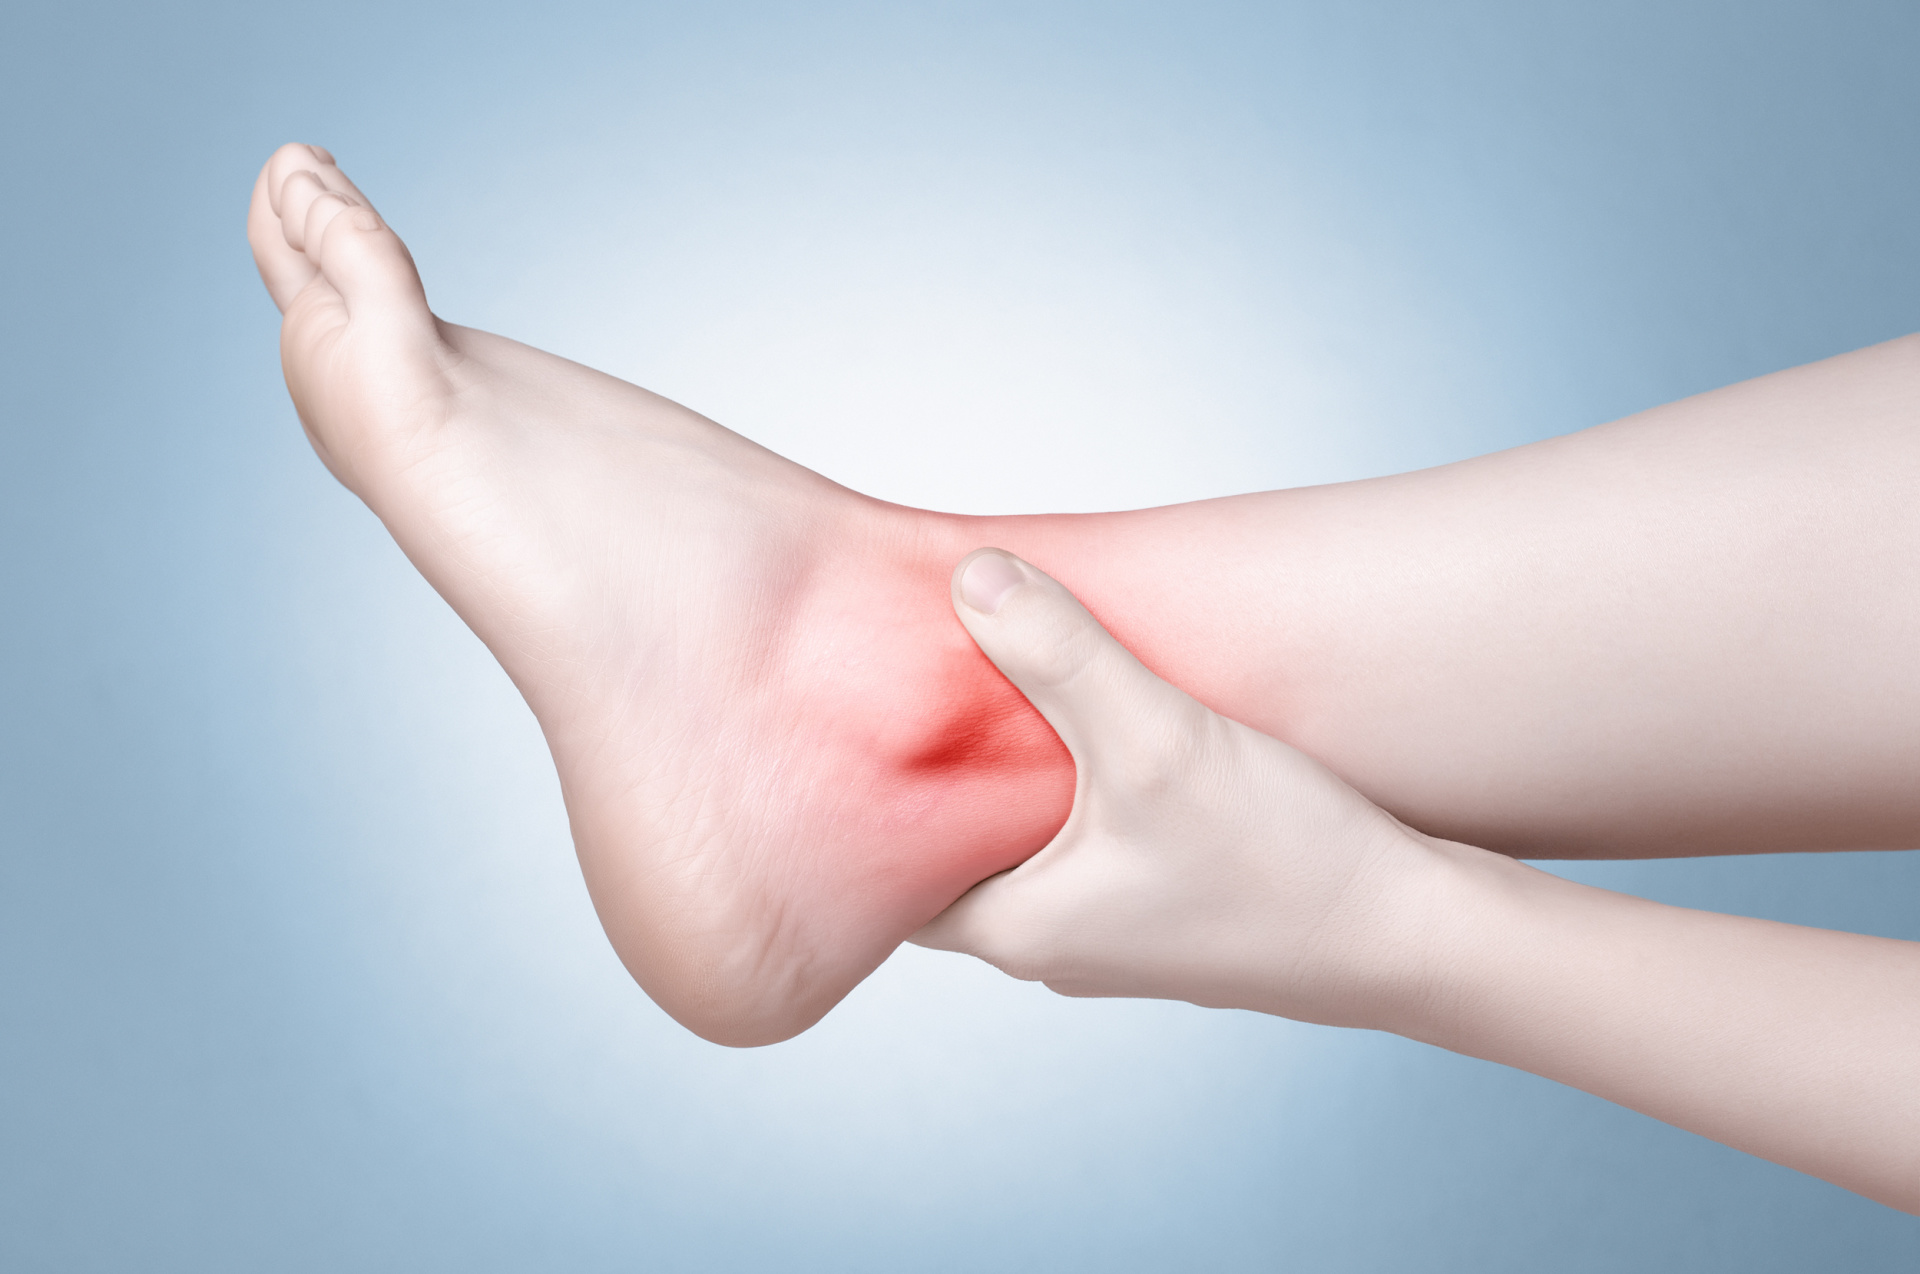

Ankle Sprain

A sprained ankle is an injury that occurs when you roll, twist or turn your ankle in an awkward way. This can stretch or tear the tough bands of tissue (ligaments) that help hold your anklebones together. Ligaments help stabilize joints, preventing excessive movement.